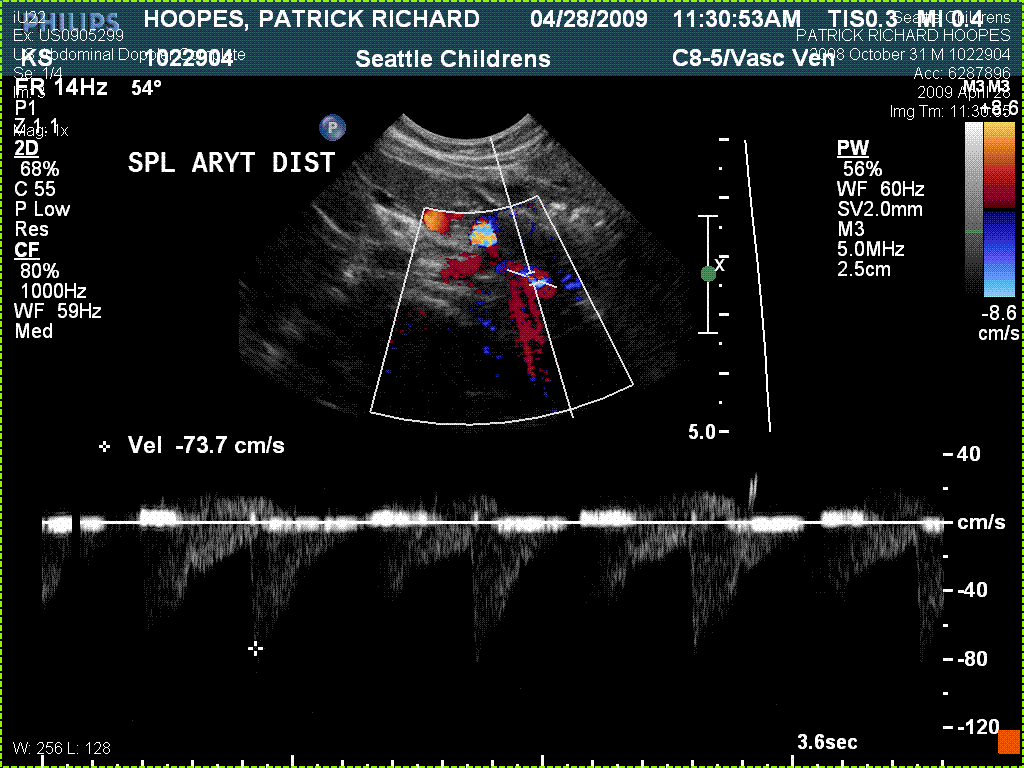

Since they don’t do intestinal transplants where we live, we have chosen to have Patrick listed at Seattle Children’s Hospital. Patrick has been on the waiting list since April of 2009. He is status 1A and will have his transplant is soon as a donor match is found.